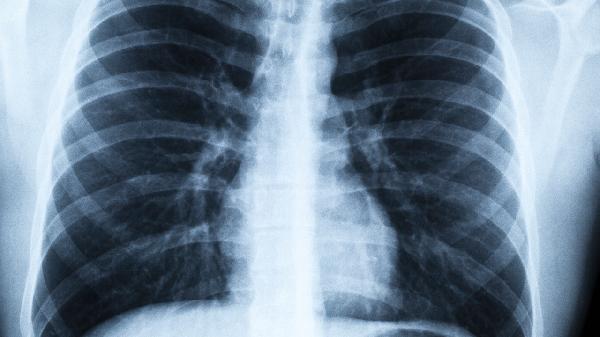

二、肺气肿的早期信号别忽视

1、晨起干咳超过两周

特别是吸烟人群出现无痰干咳,要警惕。

2、爬楼梯气短

原来能轻松爬三层楼,现在两层就喘不过气。

3、莫名消瘦

没有刻意减肥,半年内体重下降超过5%。

4、指甲变杵状

指甲盖隆起如鼓槌,是典型缺氧表现。